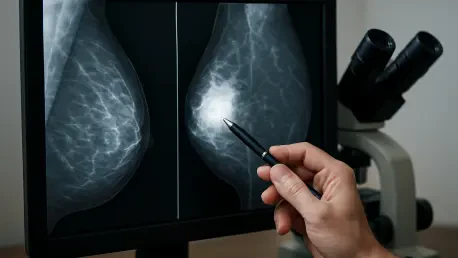

The ongoing quest for safer, more accurate breast cancer screening methods has led researchers to explore innovative alternatives to traditional mammography, which, despite its effectiveness, involves ionizing radiation. As the medical community increasingly seeks radiation-free options, the convergence of advanced imaging physics and sophisticated artificial intelligence is creating a new frontier in diagnostic capabilities. A significant breakthrough in this domain is now emerging, centering on the use of AI to automate and refine the complex processes behind novel imaging techniques. This development promises not only to enhance the precision of radiation-free scans but also to streamline clinical workflows, potentially making early and accurate detection more accessible. The integration of intelligent algorithms into technologies like acoustic computed tomography (CT) represents a pivotal step toward creating diagnostic tools that are both powerful and patient-friendly, signaling a potential paradigm shift in how breast health is monitored and managed.

Dr. Malik’s presentation, titled “Automated breast boundary extraction from reflection data in breast acoustic CT,” will provide an in-depth look at a highly sophisticated, automated algorithm. This algorithm was meticulously developed by QT Imaging to precisely delineate the breast boundary in scans produced by its Breast Acoustic CT™ system. This technological leap is far more than a simple procedural improvement; it forms a critical piece of the company’s overarching strategy to fuse advanced, physics-based imaging with the power of modern artificial intelligence and machine learning (AI/ML). The goal of this synergy is to dramatically boost the clinical value and reliability of its non-invasive imaging technology. By automating what was once a complex and variable step, the algorithm establishes a consistent and accurate foundation upon which all subsequent image processing and analysis can be built, ensuring higher quality results and paving the way for more complex AI-driven applications in the near future.

The immediate impact of this automated boundary detection algorithm is profound, as it serves as the foundational element for the entire imaging pipeline. Its precise function is essential for significantly improving the accuracy of image reconstructions, which is the process of creating a detailed picture from the raw scan data. Furthermore, the algorithm is instrumental in determining the correct gain factor for reflection imaging, a key parameter that affects image brightness and contrast. It also enables more effective denoising, filtering out irrelevant signals to produce a clearer and more interpretable image. Crucially, this automated boundary is a prerequisite for the accurate calculation of breast density, a vital biomarker for assessing breast cancer risk. Dr. Malik has emphasized that the multi-step algorithm is not only fast and efficient but has also been rigorously validated on an extensive dataset and is already fully integrated into the company’s production software, underscoring its readiness for widespread clinical use.